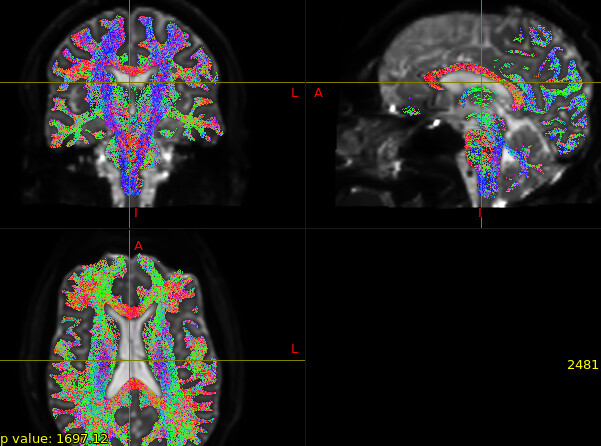

- Back to FOD-based tractography, actually the results look generally okay to my eyes (please see figure in the next comment because I can only have one image in the post) that’s why I hadn’t been worried. But yes when I examine the streamlines connecting specific pairs of ROIs, there are some errors, and seems some ROI pairs are more prone to errors. My question is, I think there is going to be some degree of errors in tractography regardless, no? And if so, to what extent it would consider acceptable? Since it’s not possible to inspect and sift through every streamline, or one should just use the method that is supposed to be more appropriate (so FOD is a no-no in our case)?